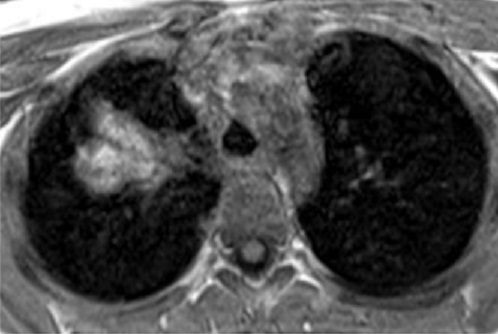

Aspect TDM de masse à

bord irregulier à isodensite heterogene du poumon

droit . Image radiologique TDM sans contrast

IV , coupe axiale |

Meme cas en coupe IRM axiale

à ponderation sur T1 . La tumeur est hyperintense

dominant heterogene |

Image radiologique de cette tumeur en

coupe IRM axiale à ponderation sur T2 |